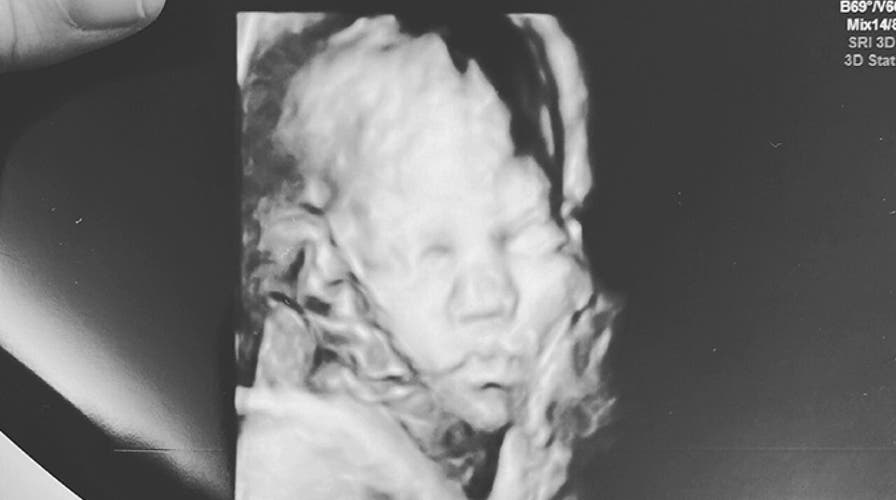

Expecting mother Rachel McKibben joins 'Fox & Friends.'